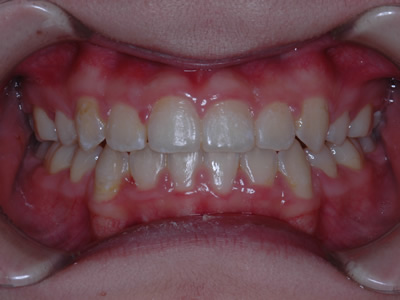

上顎の劣成長 (成長不足) による反対咬合で、上顎は拡大装置と上顎前方牽引装置を併用し前方方向への成長を促して前歯の咬み合わせを改善した後に、上下顎の前歯をマルチブラケット装置で並べました。治療の期間は2年でした。

初診時

終了時